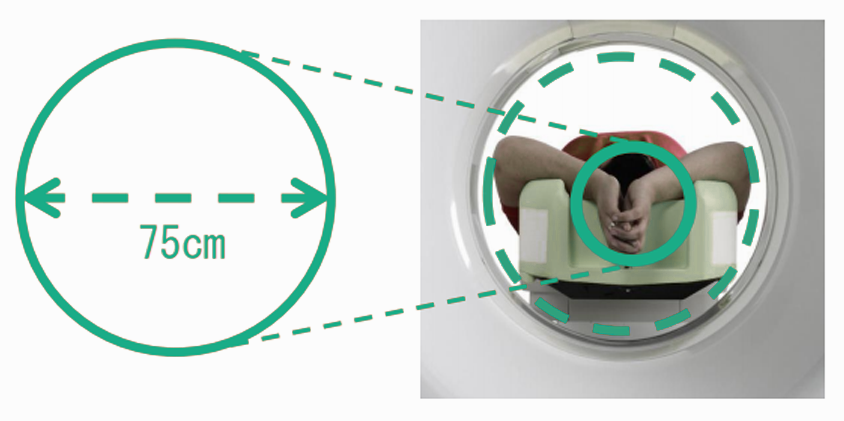

采用了最先进的驱动技术,极大的提高了信号的传输效率,确保进行快速的扫描。 机架采用标准几何设计,射线扇形角小。 机架上横断位,矢状位,冠状位三个方向定位灯,确保定位的快速准确。 采用呵护患者的先进设计,机架开口径达 750mm。